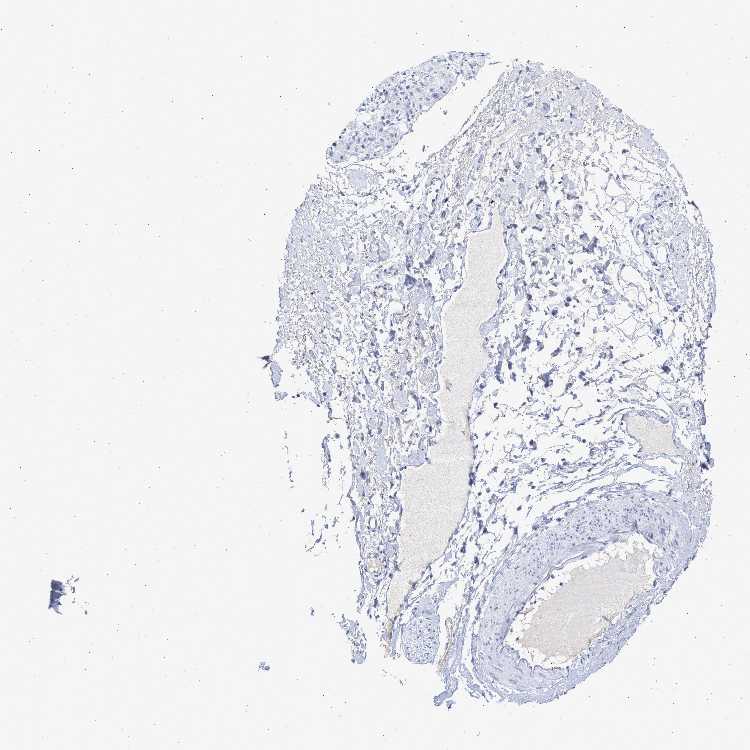

SOFT TISSUE 2 - Antibody stainingi

Antibody staining in the annotated cell types in the current human tissue is reported as not detected, low, medium, or high, based on conventional immunohistochemistry profiling in selected tissues. This score is based on the combination of the staining intensity and fraction of stained cells.

Each image is clickable and will lead to virtual microscopy that enables deeper exploration of all samples and also displays staining intensity scores, fraction scores and subcellular localization as well as patient and tissue information for each sample.

Antibody HPA016816Antibody HPA017382

Fibroblasts Not detectedNot detected

Peripheral nerve -Not detected